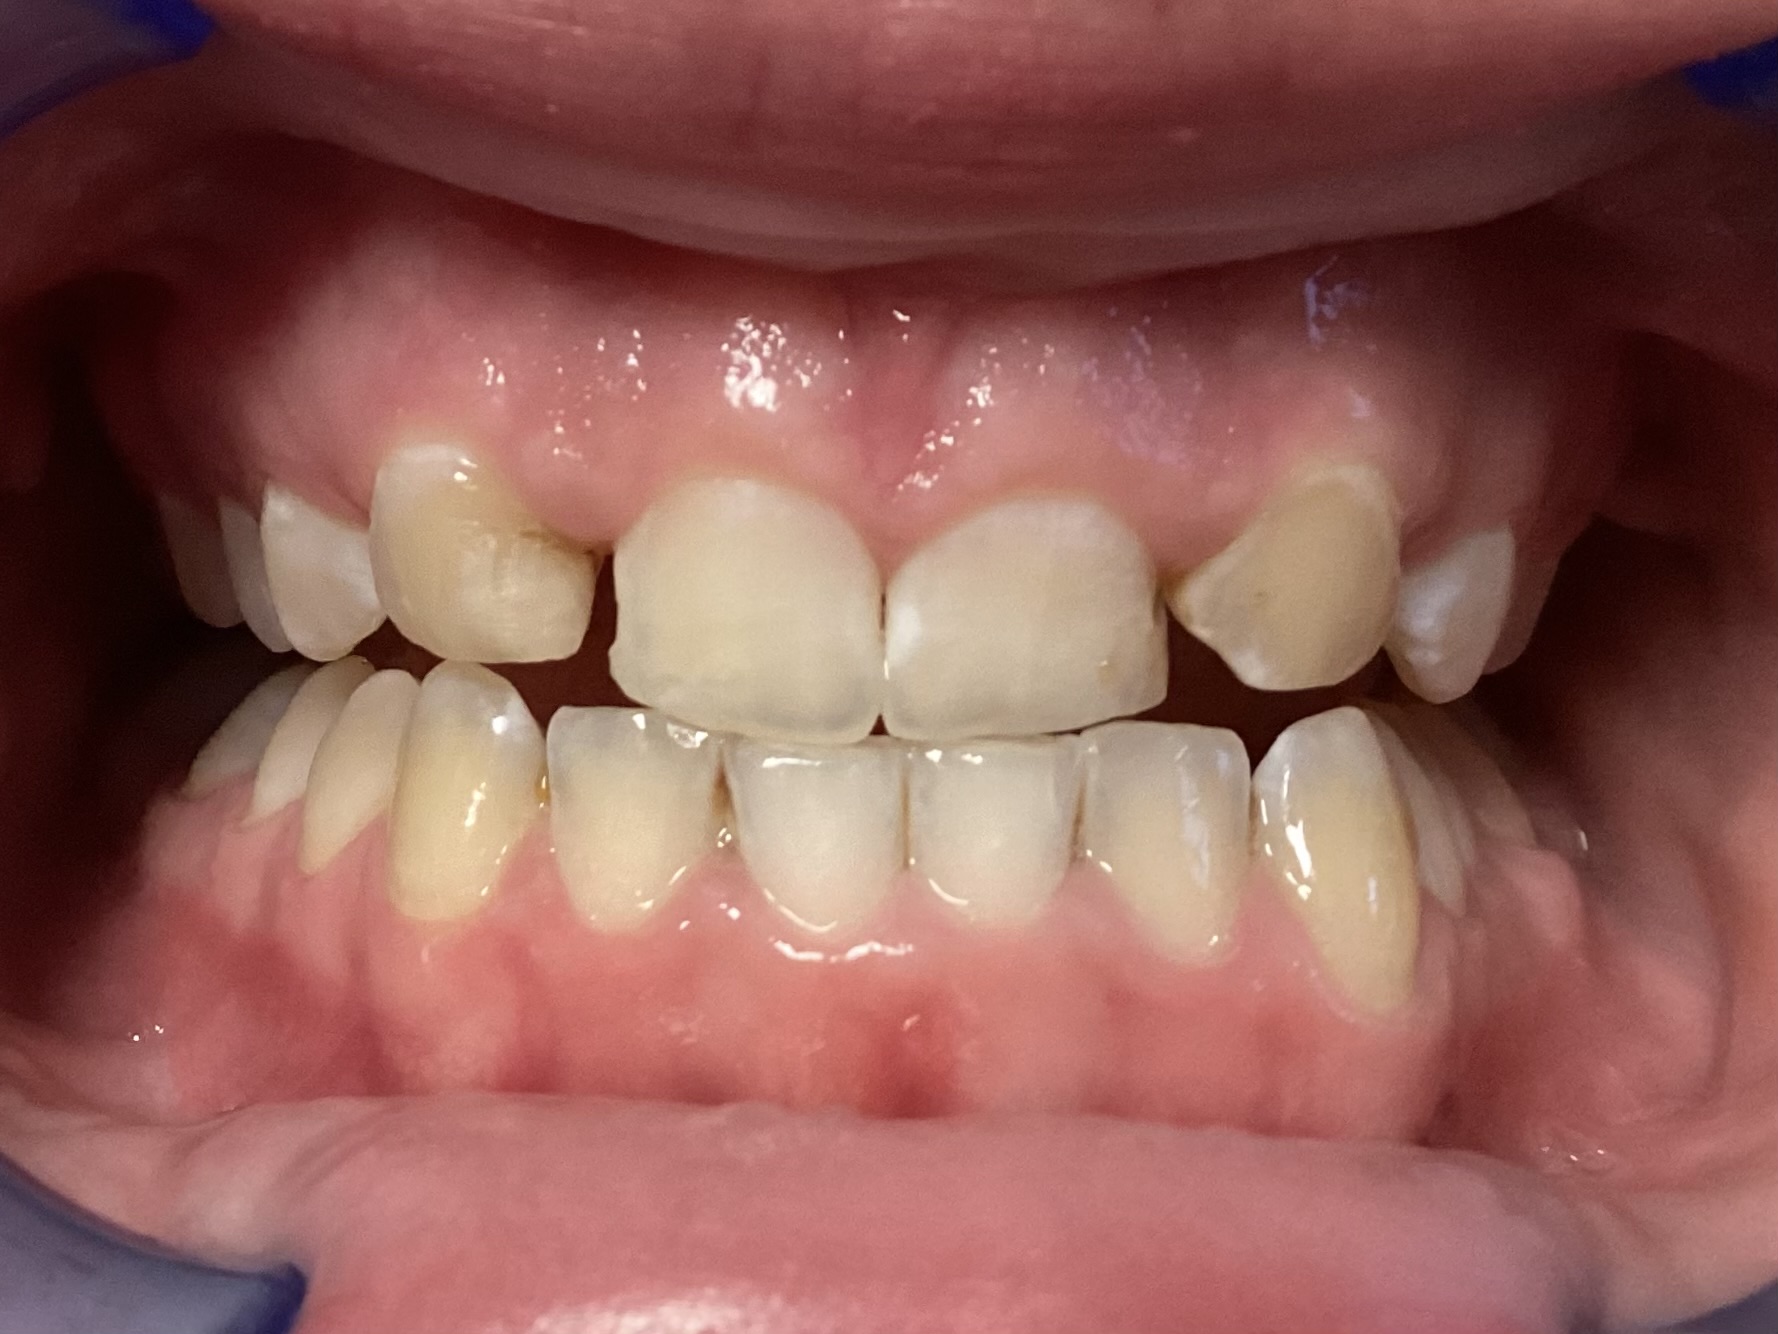

This patient arrived at my practice last week with 2 congenitally missing laterals incisors. Her orthodontist moved the canines into the position of the lateral incisors to fill the gaps but canines don’t look like incisors. They are pointy and “fat” so I told them upfront that although perfect aesthetics will not be achieved we can greatly improve the look and also remove the decay. The procedure required a single 2hr appointment and a very pleasing result was achieved with a very happy teenager leaving the practice that day. Further improvements can be done at a next visit by removing the white spots on the first premolars.